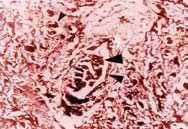

Histológicamente los cortes de los ratones sacrificados el día 1 (24 horas postobstrucción), mostraron congestión sinusoidal y vascular a nivel de los vasos portales con estasis biliar asociada en 20% de los cortes. Estas lesiones se consideraron como leves (figuras 1a, 1b). Los cortes obtenidos el día 7 mostraron acumulación de pigmento biliar en colangiolos y zona pericolangiolar, con proliferación portal de colágeno en 60% de los cortes. Estas lesiones sumadas a las consideradas leves, se refieren como lesiones moderadas (figuras 1c, 1d). En los cortes de los tejidos de los ratones sacrificados el día 15 postobstrucción, además de las lesiones observadas en los días 1 y 7, se encontró proliferación hamartomatosa de colangiolos y fibrosis portal en conductos biliares, placa limitante y lóbulos en 15% de los cortes. Estas lesiones se clasificaron como severas (figuras 2a, 2b, 2c, 2d). Las lesiones observadas a nivel de cerebro, corazón y pulmones se debieron a congestión vascular y dilatación en varios grados. Los riñones mostraron precipitación de pigmento biliar en los túbulos colectores al día 15 de sacrificio. El grupo control presentó morfología macroscópica y microscópica hepática normal.

Figura 1c. Trombo biliar asociado con fibrosis periductal (flecha grande) mononucleares y fibroblastos (flecha pequeña).

Figura 1d. Proceso fibrótico en porción centrolobular que se extiende a todo el lóbulo.